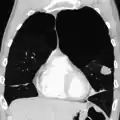

A chest X-ray is not useful to establish a diagnosis of COPD but it is of use in either excluding other conditions or including comorbidities such as pulmonary fibrosis and bronchiectasis. Characteristic signs of COPD on X-ray include hyperinflation (shown by a flattened diaphragm and an increased retrosternal air space) and lung hyperlucency.[5] A saber-sheath trachea may also be shown that is indicative of COPD.[110]

A CT scan is not routinely used except for the exclusion of bronchiectasis.[5] An analysis of arterial blood is used to determine the need for oxygen supplementation and assess for high levels of carbon dioxide in the blood; this is recommended in those with an FEV1 less than 35% predicted, those with a peripheral oxygen saturation less than 92% and those with symptoms of congestive heart failure.[111] WHO recommends that all those diagnosed with COPD be screened for alpha-1 antitrypsin deficiency.[42]